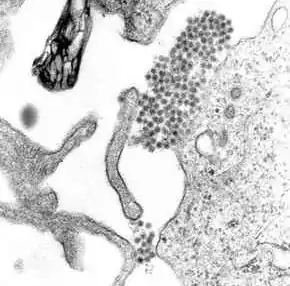

Viral replication

Once inside the skin, dengue virus binds to Langerhans cells (a population of dendritic cells in the skin that identifies pathogens).[48] The virus enters the cells through binding between viral proteins and membrane proteins on the Langerhans cell, specifically, the C-type lectins called DC-SIGN, mannose receptor and CLEC5A.[32] DC-SIGN, a non-specific receptor for foreign material on dendritic cells, seems to be the main point of entry.[35] The dendritic cell moves to the nearest lymph node. Meanwhile, the virus genome is translated in membrane-bound vesicles on the cell's endoplasmic reticulum, where the cell's protein synthesis apparatus produces new viral proteins that replicate the viral RNA and begin to form viral particles. Immature virus particles are transported to the Golgi apparatus, the part of the cell where some of the proteins receive necessary sugar chains (glycoproteins). The now mature new viruses are released by exocytosis. They are then able to enter other white blood cells, such as monocytes and macrophages.[32]